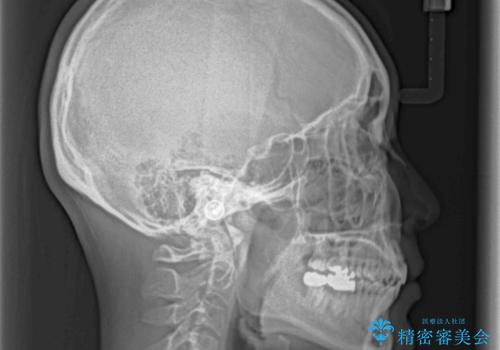

- 奥歯の虫歯と前歯のデコボコや突出感を気にして来院された患者様です。

上顎歯列が、下顎に対して前方にありましたが、口元に出っ歯の印象がなかったため、親知らずを抜歯した上で、上顎歯列全体を後方に移動させることとしました。

咬合力が強いため、アンカースクリューを使用し、ワイヤー装置にて矯正治療を行うこととしました。